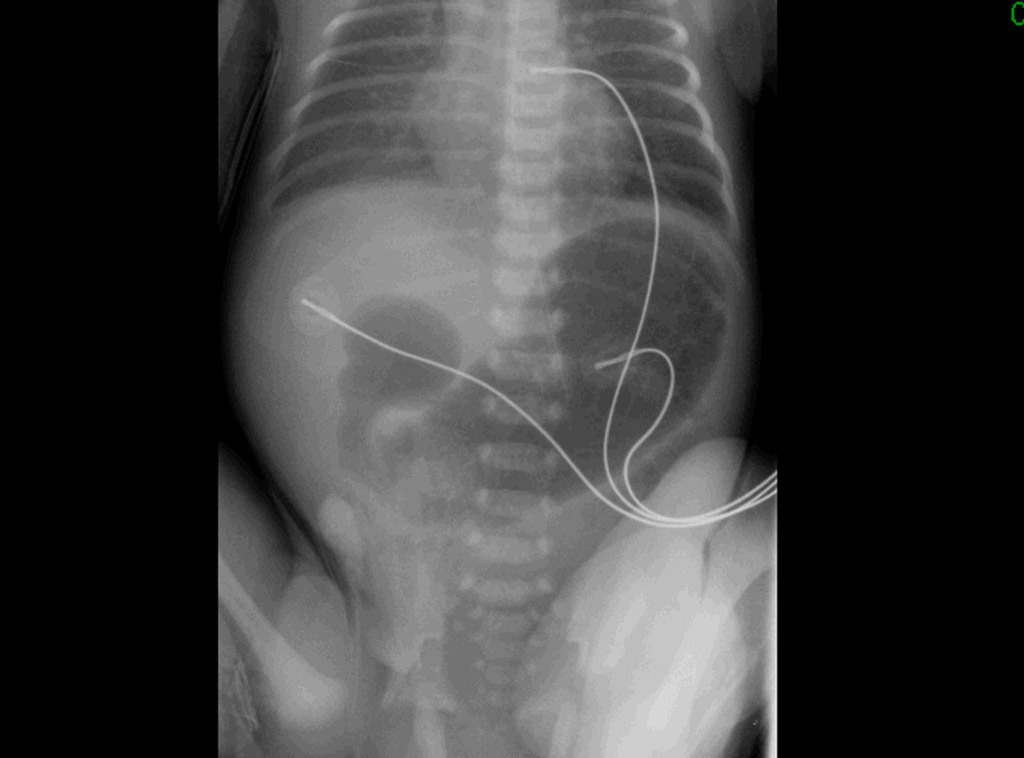

– ASP : double bulle ;